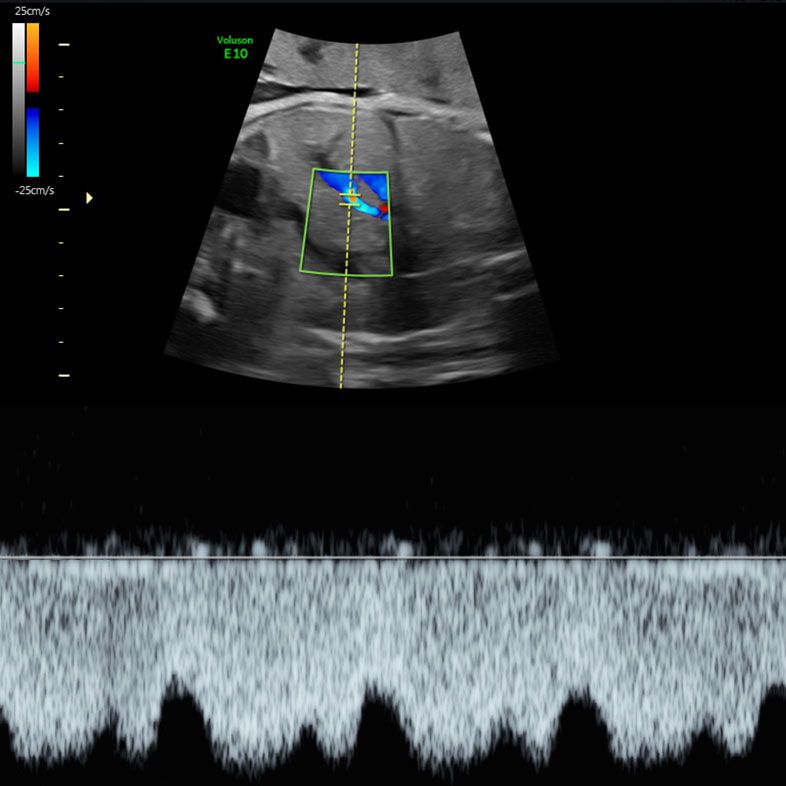

Examination of the heart (quality of the scan depends on fetal position) with colour Doppler flow imaging (looking at how the blood flows through the heart),

- A fetal wellbeing examination (fetal movements, amniotic fluid, and fetal Dopplers used to detect the fetal heartbeat),

Fetal Doppler studies of Ductus Venosus blood flow at our Wellbeing Scan